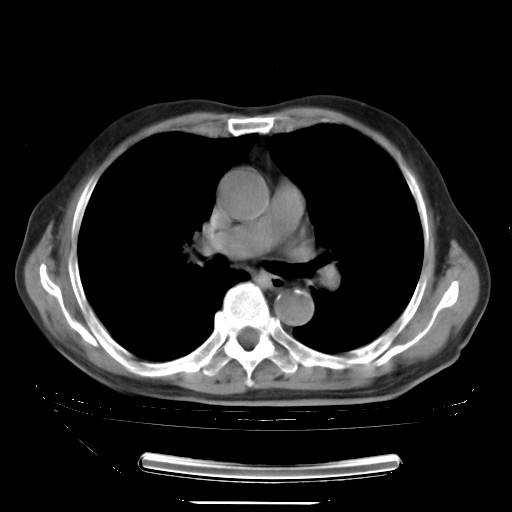

今天复查肺部CT,发现双肺广泛磨玻璃样改变。所以我把3月19日和5月9日相隔50天的肺部CT上传。请大家会诊。

2009年3月19日肺部CT片。

2009年3月19日肺部CT